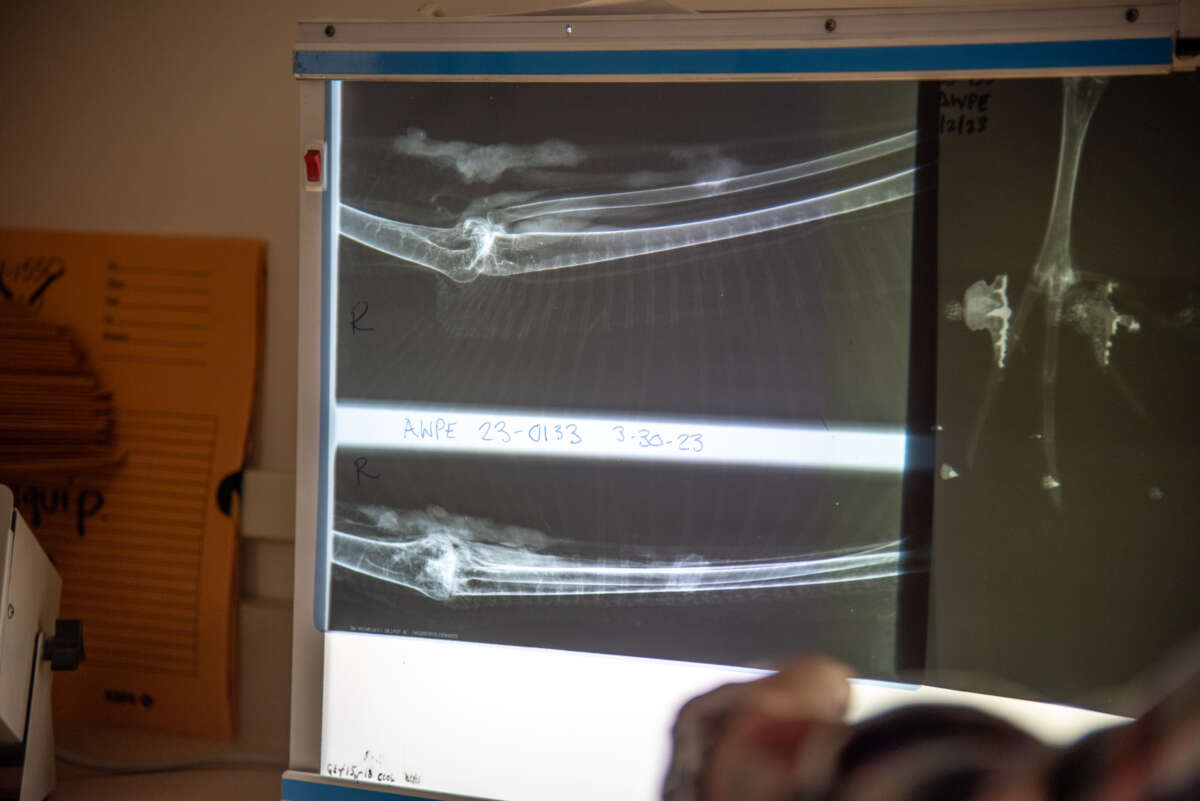

This pelican had an injury caused by a fishing hook and fishing line—the most common cause of injury that IBR deals with on a daily basis. Fishing hooks often become embedded in pelican beaks, and fishing line can cause lacerations across their body as they attempt to untangle themselves. The first step of a bird’s treatment is processing, where hospital staff examine each bird to figure out what’s wrong. This can include a physical exam for any breaks or emaciation, a white / red blood cell count to check for infection, anti-parasite treatment, and much more. For any potential skeletal problems, x-rays are also taken. Our released pelican had a prior hairline fracture that became a fully broken leg during treatment. Luckily, birds have lightning-fast metabolisms—a break that may have taken a human up to six months to heal took only three weeks on this pelican.

X-rays of the released pelican’s hairline fracture (seen running horizontally in the lower image)